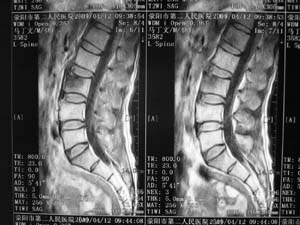

标题: MRI2131:男,腰痛三月向右下肢放射一月余

骨质轻微破坏,硬化明显,椎管未见异常,考虑良性骨瘤的可能性大,

椎体增生 硬化 囊变。考虑:退变!

支持考虑退变,许莫结节形成

椎体前缘骨质增生硬化、囊变。椎旁软组织未见确切异常。考虑椎体前缘软骨结节。

1)l3椎体前上缘许莫氏结节形成。2)腰椎退行性改变。

l3椎体前上缘许氏结节。

退变,许莫氏结节.腰1椎体血管瘤.

l2大部分椎体信号增高-----脂肪变性,转移待排。l3 椎体t2 低信号考虑硬化增生。